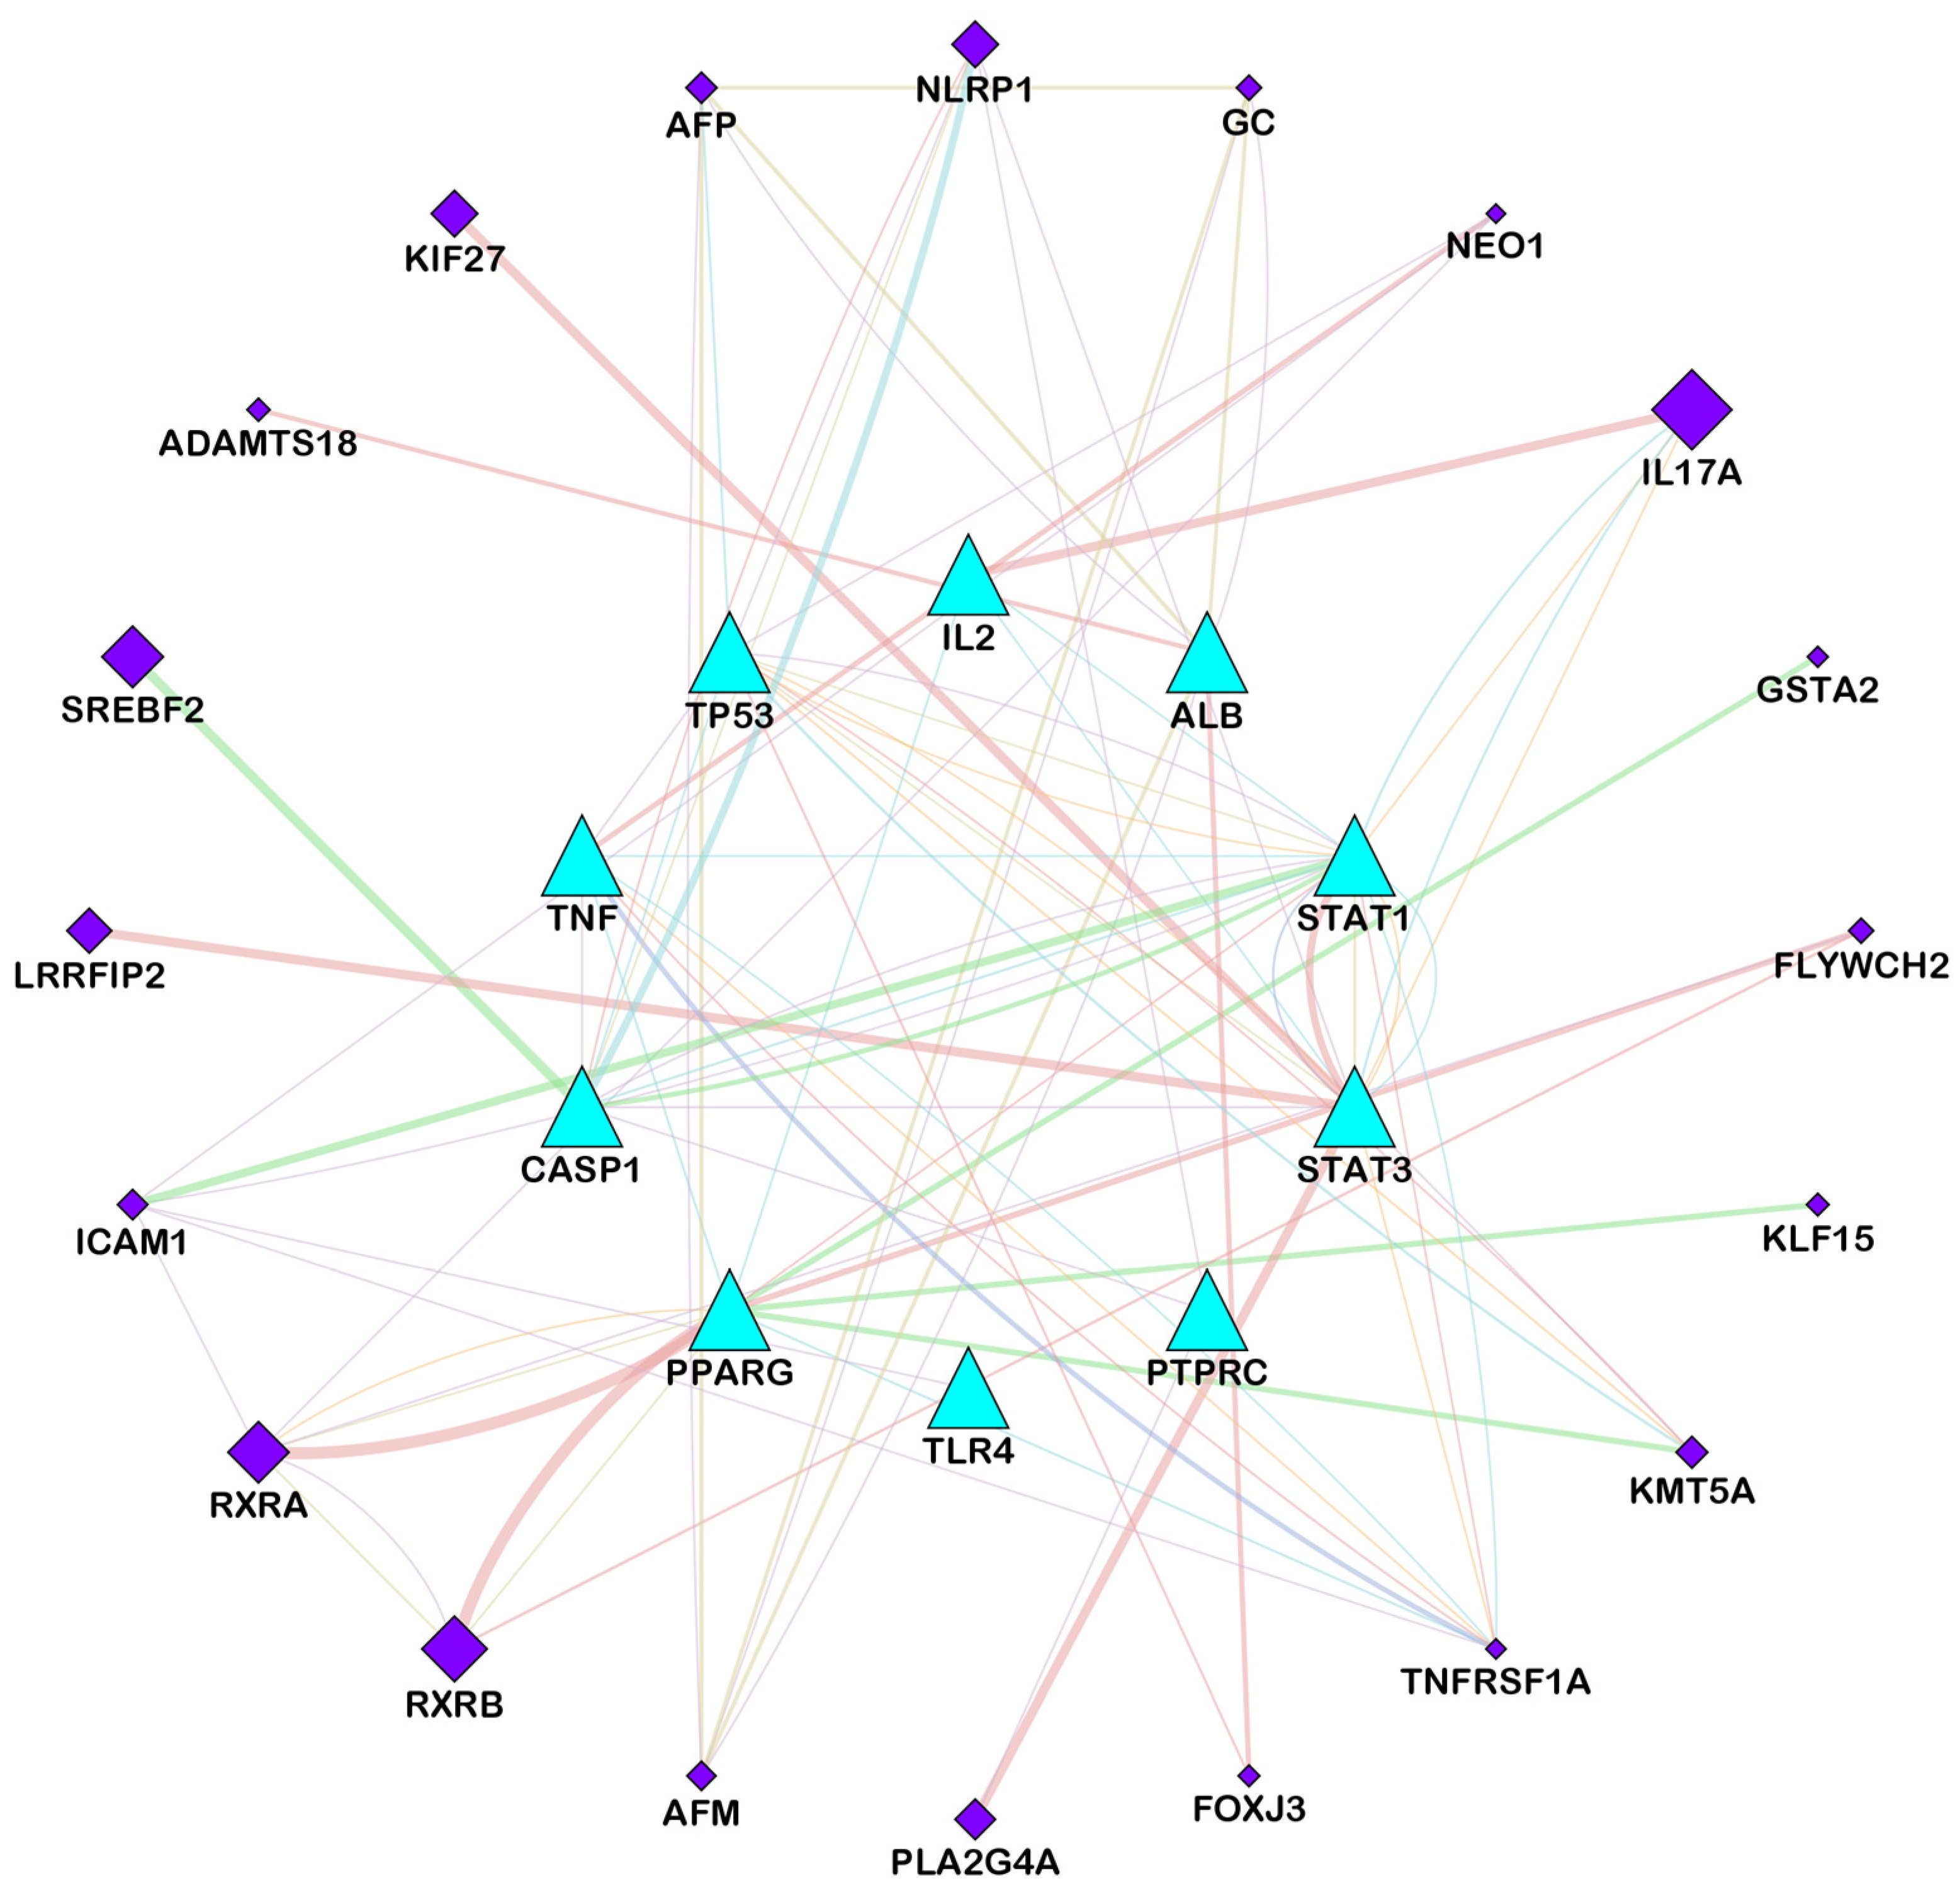

3.2. Compound–Disease Common Target Network Construction and Analysis

3.3. Analysis of Functional and Pathway Enrichment

| STAT3 (signal transducer and activator of transcription 3) | Suppresses inflammation and tissue damage caused by fungal infection | STAT3 is a transcription factor that can modulate the immune response and prevent excessive inflammation and tissue damage. STAT3 can also inhibit the growth and invasion of C. albicans by regulating the expression of anti-fungal genes and enhancing the phagocytosis of fungal cells. Ajwa date extract may stimulate the release of STAT3 and enhance its anti-fungal activity. | [90,91] |

| IL-2 (interleukin-2) | Promotes T cell activation and proliferation against fungal infection | IL-2 is a cytokine that can stimulate the activation and proliferation of T cells, which are immune cells that can recognize and kill infected cells. IL-2 can also enhance the production of other cytokines that have anti-fungal effects, such as IFN-gamma and TNF-alpha. Ajwa date extract may stimulate the release of IL-2 and increase its anti-fungal function. | [69,70] |

| PTPRC (protein tyrosine phosphatase receptor type C) | Regulates T cell receptor signaling and immune response against fungal infection | PTPRC, also known as CD45, is a protein that can regulate the signaling of T cell receptor (TCR), which is a molecule that recognizes antigens presented by infected cells. PTPRC can modulate the activation and differentiation of T cells and their anti-fungal effector functions. Ajwa date extract may stimulate the release of PTPRC and improve its anti-fungal function. | [71,72] |

| STAT1 (signal transducer and activator of transcription 1) | Activates anti-fungal genes and enhances the phagocytosis of fungal cells | STAT1 is a transcription factor that can activate the expression of genes that are involved in anti-fungal responses, such as IFN-gamma, NOS2 and CXCL10. STAT1 can also enhance the phagocytosis of fungal cells by macrophages, which are immune cells that can engulf and destroy foreign particles. Ajwa date extract may stimulate the release of STAT1 and increase its anti-fungal function. | [90,92] |

| CASP1 (caspase-1) | Induces the pyroptosis (inflammatory cell death) of infected cells and prevents fungal dissemination | CASP1 is a protein that can trigger pyroptosis, which is a process of inflammatory cell death, in the response to fungal infection. Pyroptosis can help eliminate infected cells and prevent the spread of fungal pathogens. Pyroptosis can also release cytokines, such as IL-1beta and IL-18, that have anti-fungal effects. Ajwa date extract may stimulate the release of CASP1 and increase its pyroptotic function. | [74] |

| ALB (albumin) | Binds to fungal toxins and neutralizes their effects | ALB is a protein that can bind to various substances in the blood, including fungal toxins such as gliotoxin and fumagillin. ALB can neutralize the effects of these toxins on immune cells and tissues. Ajwa date extract may stimulate the release of ALB and enhance its anti-toxin activity. | [75] |

| TP53 (tumor protein p53) | Induces the apoptosis (cell death) of infected cells and prevents fungal dissemination | TP53 is a protein that can trigger apoptosis, which is a process of programmed cell death, in response to DNA damage or stress. Apoptosis can help eliminate infected cells and prevent the spread of fungal pathogens. Ajwa date extract may stimulate the release of TP53 and increase its apoptotic function. | [93] |

| TLR4 (Toll-like receptor 4) | Recognizes fungal components and activates the inflammatory response against fungal infection | TLR4 is a protein that can recognize fungal components such as lipopolysaccharide and beta-glucan. TLR4 can activate the inflammatory response against fungal infection by inducing the expression of cytokines such as TNF-alpha, IL-1beta, IL-6, IL-12 and IL-23. Ajwa date extract may stimulate the release of TLR4 and increase its anti-fungal function. | [77] |

| TNF (tumor necrosis factor) | Induces inflammation and cell death against fungal infection | TNF is a cytokine that can induce inflammation and cell death against fungal infection by activating the expression of genes such as NOS2, CXCL10 and ICAM1. TNF can also enhance the phagocytosis of fungal cells by macrophages and neutrophils. Ajwa date extract may stimulate the release of TNF and increase its anti-fungal function. | [78] |

| PPARG (peroxisome proliferator-activated receptor gamma) | Inhibits fungal growth and biofilm formation | PPARG is a protein that can inhibit the growth and biofilm formation of C. albicans by regulating the expression of genes such as EFG1, NRG1 and HWP1. PPARG can also modulate the immune response and inflammation against fungal infection by influencing the production of cytokines such as IL-10, IL-17 and TGF-beta. Ajwa date extract may stimulate the release of PPARG and increase its anti-fungal function. | [79] |